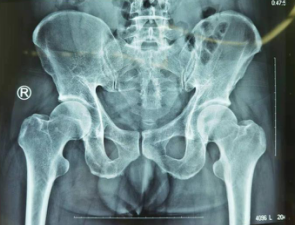

1月29日,急诊科来了一名男性患者。患者驾驶货车时不幸受伤,骨盆骨折,由我院创伤骨科收治。

患者来院前,先在当地医院就诊,进行了相关检查,诊断骨盆骨折。因当地医院医疗条件有限,医生建议其立即到三级骨科医院betway在线登陆治疗。

创伤骨科任海东主任接诊,了解情况后,为患者制定了详细的手术方案,并完善各项术前检查。2月4日一早,任海东主任、信远医生手术团队为患者进行了天玑机器人导航下骨盆骨折复位内固定术。